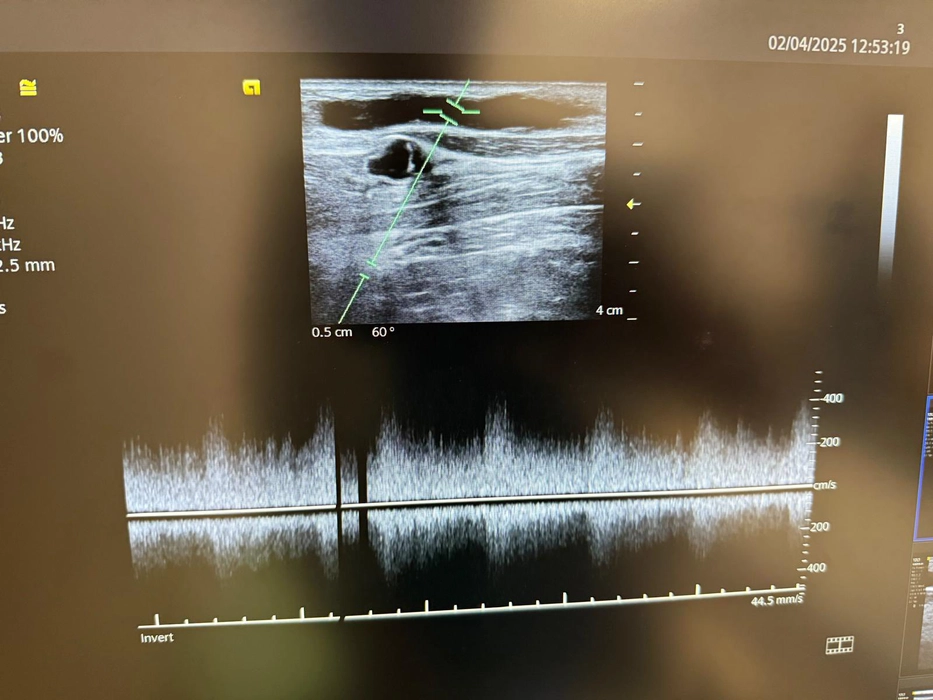

Nephrois – Clinca de Nefrologie Iasi condusă de medicul ieșean Adrian Covic a salvat accesul pentru dializă al unui pacient